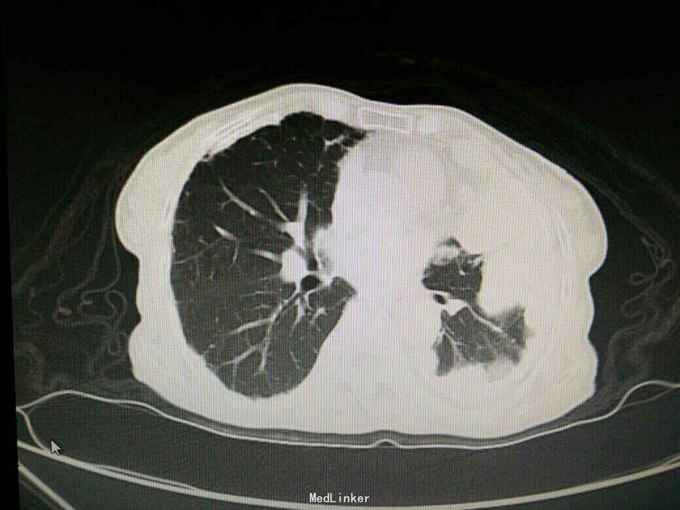

患者陈某某,女,69岁。 主诉:反复咳嗽咳痰1年余,加重伴气促1月。 病史:1年前出现咳嗽咳痰,阵发性,少量白痰,无发热,无盗汗消瘦,无胸闷胸痛,未予重视。1月余前出现咳嗽咳痰加重,伴气促,活动后明显,无夜间阵发性呼吸困难,当地医院胸片示左侧胸膜多发肿块,两侧胸膜增厚钙化,随后至我院就诊。 既往史: 有石棉接触史20余年,40年前行输卵管结扎术,26年前行阑尾切除术,否认其他疾病史,否认烟酒史。

查体:神志清,精神可,生命体征平稳。两肺呼吸音粗,未闻及干湿性啰音。 辅查: 血气分析:PH7.43, 二氧化碳分压43mmHg, 氧分压77mmHg, 氧饱和度95%。 血常规:WBC7.5x10∧9/L, NE77.8%, Hb132g/L, plt231x10∧9/L。 尿常规,粪便常规,凝血功能,肿瘤标志物,CRP, 免疫功能,肝肾功能电解质无明显异常。 痰培养,痰找抗酸杆菌阴性。 心电图无明显异常。 心脏彩超:主动脉瓣局部退行性变,左室舒张功能减退,轻度肺高压。 腹部B超无异常。 胸部增强CT:双侧多发胸膜斑,左侧胸膜弥漫结节状及团块形成,考虑石棉肺伴左侧胸膜继发性恶性间皮瘤可能。

入院诊断:左侧胸膜肿物:胸膜间皮瘤? 诊治经过:予对症支持治疗,行CT引导下胸膜活检 病理:结合免疫组化和临床病史,符合恶性间皮瘤。 治疗:患者明确诊断后予化疗前预处理,择期行培美曲塞+铂类化疗